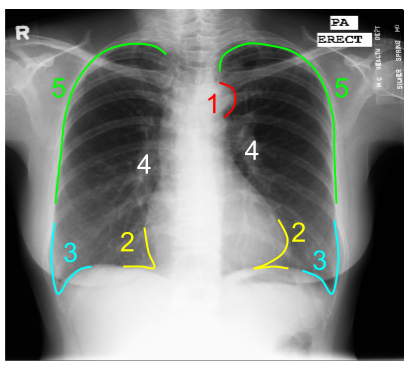

Chest x ray with labels. How to Read a Chest X Ray (with Pictures) - wikiHow Check for and mentally notate each side of the chest x-ray. 2 Position the posteroanterior and lateral x-rays. A normal chest x-ray will consist of both posteroanterior (PA) and lateral films which are read together. Align them so they are viewed as if the patient were standing in front of you, so their right side would be facing your left. [3] Reading Chest X-Rays - Anatomy Labelled Reading a ... | GrepMed Description Reading Chest X-Rays - Anatomy Labelled Reading a chest x-ray (CXR) is an incredibly important aspect of acute care medicine and a skill that all healthcare providers should at least have some comfort in doing. Chest X-Ray: What to Expect, Diagnosis, Safety, Results - Cleveland Clinic A chest X-ray uses a focused beam of radiation to look at your heart, lungs and bones. Healthcare providers use chest X-rays to diagnose or treat conditions like pneumonia, emphysema or COPD. Chest X-rays are quick, noninvasive tests. Usually, you will know the results of your X-ray within one to two days. Appointment Center 24/7 216.445.7050 Normal chest X-ray with labels - Stock Image - C036/6419 Normal chest X-ray with labels. C036/6419. Rights Managed. 34.9 MB (2.9 MB compressed) 3922 x 3112 pixels. 33.3 x 26.4 cm ⏐ 13.1 x 10.4 in (300dpi) Request Price Add To Basket ADD TO BOARD.

Normal Chest X-Ray • LITFL Medical Blog • Labelled Radiology Labelled normal anatomy chest X-ray to assist in interpretation review Further reading CCC - Chest x-ray interpretation Labelled normal Chest X-ray DRSABCDE of CXR Interpretation ABC of CXR Interpretation Top 150 CXR Quiz Chest X-ray for the OSCE Dr Eric Strong Vodcast series on CXR Interpretation Tor Ercleve Normal chest x-ray: Anatomy tutorial | Kenhub Contents Step 1: Determine the view Step 2: Determining image quality Rotation Inspiration Penetration Step 3: Following a systematic approach Air, airway, apices Bones Cardiac shadow, cardiovascular system Diaphragm Edges, effusions, extrathoracic soft tissues Foreign bodies Gastric bubble, great vessels Hilum Impression Clinical notes Chest X-ray Interpretation | A Structured Approach | Radiology | OSCE Begin chest X-ray interpretation by checking the following details: Patient details: name, date of birth and unique identification number. Date and time the film was taken Previous imaging: useful for comparison. Assess image quality Next, you should assess the quality of the image: a mnemonic you may find useful is ' RIPE '. Rotation What Does a Chest X-Ray Show? Pneumonia, Heart, Cancer - MedicineNet Chest X-rays can detect some lung and heart abnormalities like tumors, as well as rib fractures. A chest X-ray is most commonly used to detect abnormalities in the lungs, but can also detect abnormalities in the heart, aorta, and the bones of the thoracic area. Extra metallic objects, such as jewelry are removed from the chest and neck areas ...

Chest (PA view) | Radiology Reference Article | Radiopaedia.org The posteroanterior (PA) chest view examines the lungs, bony thoracic cavity, mediastinum and great vessels. Indications The chest x-ray is the most common radiological investigation in the emergency department 1. The PA view is frequently used to aid in diagnosing a range of acute and chronic conditions involving all organs of the thoracic cavity.